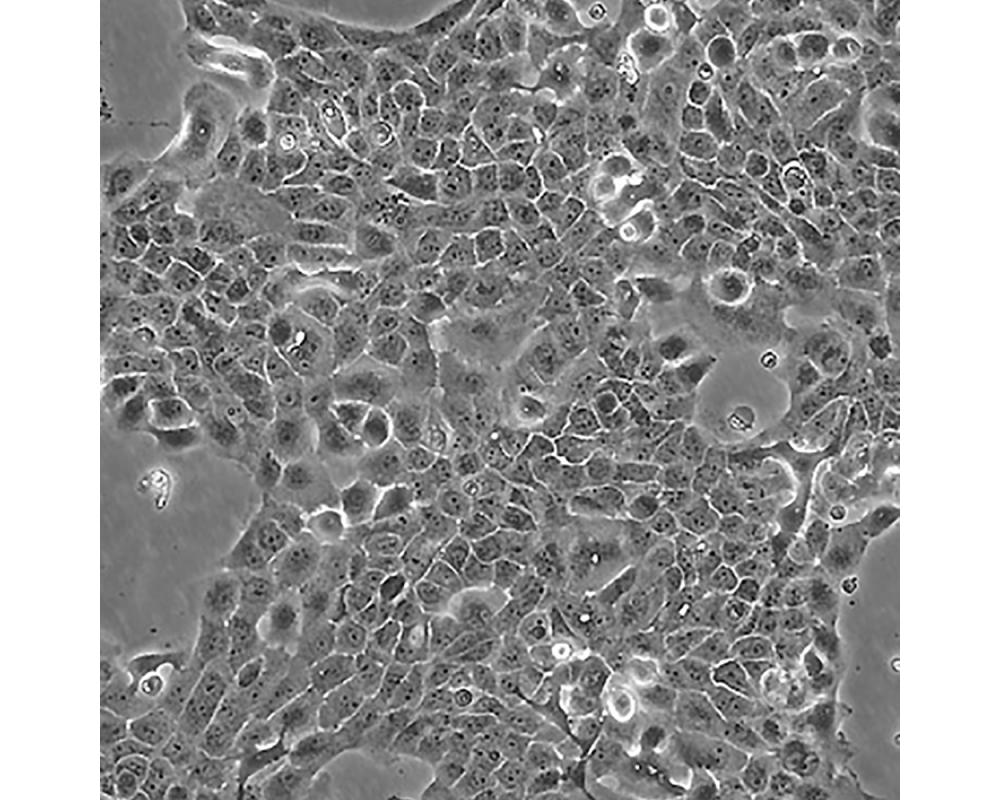

A-431(A431,A 431)

中文名稱 人皮膚鱗癌細胞

組織來源 外陰鱗狀細胞癌;女性

生長特性 adherent

形態特征 epithelial

細胞描述 該細胞源自一位患有皮膚鱗狀細胞癌的85歲女性,是GiardDJ等人建立的一系列細胞株中的一株。該細胞在免疫抑制小鼠體內可成瘤,在瓊脂上培養可形成克隆;是一個超三倍體人細胞株。